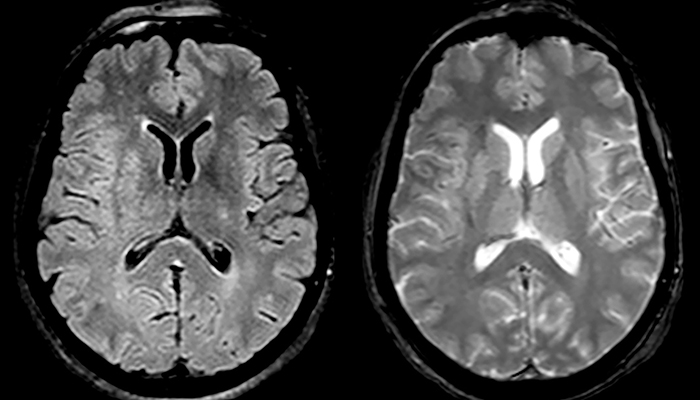

“Ingenia provides great flexibility in the parameters setting. We can tune a sequence the way we want,” says Dr. Savatovsky. “For example, in a stroke exam we use a FLAIR sequence of about two minutes instead of the four-minute FLAIR we use for MS. The diffusion is 30 seconds, the T2*-weighted scan is 30 seconds, the angiography scan time is less than one minute. Ingenia is a great scanner in that situation; even with these fast sequences we can achieve good images with good SNR. When the first sequence tells us that it’s not an ischemic stroke but a hemorrhagic stroke, we may switch to a time-resolved angiography to look for vascular malformations and venous thrombosis.

“Every center is different, but for me the ideal protocol for stroke includes diffusion weighted imaging, FLAIR, and fast susceptibility imaging,” says Dr. Savatovsky. “Our fast susceptibility weighted imaging takes 50 seconds, so it’s as fast as T2*-weighted imaging. It visualizes hemorrhage but also the clots. We also do 3D MR angiography that provides information on cervical and brain vessels. If the patient does not need immediate treatment, or if additional information is needed to decide on treatment, we might also add perfusion imaging and post-contrast T1-weighted imaging.”